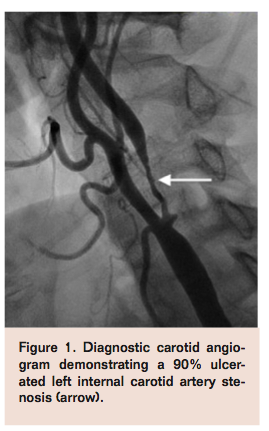

The patient was brought to the angiography suite for elective carotid artery stenting in the setting of recurrent embolic events. Vascular access was obtained in the right common femoral artery with a 10 Fr sheath and the right femoral vein with a 6 Fr sheath. A 6 Fr internal mammary diagnostic catheter was used to selectively engage the left common carotid artery (CCA) and diagnostic angiogram revealed a 90% ulcerated stenosis in the proximal left ICA (Figure 1) with preserved intracerebral flow. A stiff angled glidewire (Terumo) was advanced into the left external carotid artery (ECA) to allow exchange for the 9.5 Fr CCA balloon sheath (Gore) into the left CCA through the 10 Fr arterial sheath. An ECA balloon wire (Gore) was then positioned at the ostium of the left ECA. Carotid flow reversal was initiated after inflation of the CCA and ECA balloons (Figure 2) with retrograde flow through the left ICA and CCA and continuous flow through the external filter into the venous system via the 6 Fr venous sheath. A Prowater guidewire (Abbott Vascular) was advanced through the left ICA lesion into the distal segment of the artery. A Viatrac 4 mm x 30 mm balloon (Abbott Vascular) was used to predilate the lesion